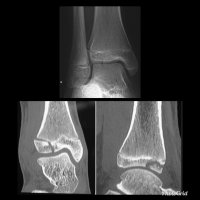

A Tillaux fracture is a traumatic Salter–Harris type III fracture through the anterolateral aspect of the distal tibial epiphysis, with variable amounts of displacement.

It accounts for 3-5% of pediatric ankle fractures and more commonly seen in girls. Tillaux feacture is seen in children nearing skeletal maturity (12-14 years old), when the medial epiphysis had closed but before the lateral side has done so.

The fracture commonly results from an abduction-external rotation force, causing the anterior tibiofibular ligament to avulse the anterolateral corner of the distal tibial epiphysis, at the opposite end to a Wagstaffe-Le Fort avulsion fracture, resulting in a Salter Harris Type III fracture.

Variability in fracture pattern is due to progression of physeal closure as anterolateral part of distal tibial physis is the last to close. When the lateral physis is the only portion not fused, external rotation may lead to Tillaux or Triplane fractures. Lack of coronal plane fracture in the posterior distal tibial metaphysis distinguishes this fracture from a triplane fracture.

Associated conditions commonly seen with this fracture are distal fibular fracture (usually SH I or II) and ipsilateral tibial shaft fracture.

If the displacement at fracture is less than 2 mm, it may be managed conservatively. However, displacement requires open reduction and internal fixation, especially when displacement is over 2 mm.

As with any intra-articular fracture if a step is left in the articular surface, then the joint will go on to premature secondary osteoarthritis.

This fracture pattern is named after Paul Jules Tillaux, a French Anatomist and Surgeon (1834-1904).